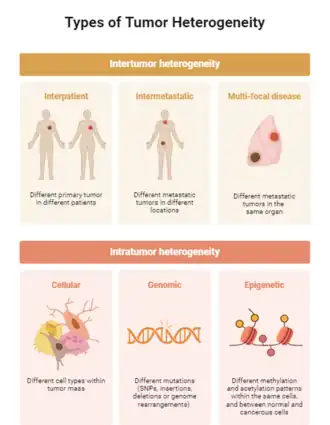

1. Heterogeneidade tumoral como razão evolutiva na evasão imunológica[37]

No câncer, muitas células tumorais estão em constante divisão. A heterogeneidade tumoral está relacionada às variações entre tais células, no que diz respeito ao genótipo e fenótipo, incluindo a taxa de divisão, o nível de malignidade e a resposta a diferentes estímulos externos. A classificação da heterogeneidade pode ocorrer em diversos níveis: entre indivíduos distintos, entre tumores primários e metastáticos, e até mesmo entre células em diferentes regiões do mesmo tumor. Consequentemente, devido às especificidades de cada indivíduo, a mesma doença pode ser diferente em pacientes diferentes. Dependendo das características, a heterogeneidade pode ser categorizada como temporal ou espacial, portanto, ocorre entre um tumor primário e o que metastatizou em outro lugar, ou entre células diferentes, mesmo em um tumor, respectivamente. [26]

A instabilidade genômica, Herança epigenética, DNA extracromossômico e microambiente são responsáveis por causar a heterogeneidade.[26] A instabilidade genômica resulta em um aumento na probabilidade e taxa de mutações nas células tumorais, causando a produção de múltiplos subclones tumorais; em relação a herança epigenética, os intensificadores e promotores diversificam os produtos expressos, afetando a transcrição de genes celulares, fazendo as células exibirem heterogeneidade, ou seja, pode-se, efetivamente, estimar a heterogeneidade dos tumores; As células tumorais apresentam uma diversidade de ecDNA, contribuindo, grandemente, para a formação da heterogeneidade; por fim, o microambiente se correlaciona com a teoria da evolução de Darwin, uma vez que, quando o câncer metastatiza no corpo, as células que sobrevivem também apresentam mutações para se adaptarem ao ambiente devido ao diferente microambiente imunológico do câncer primário e metastático, proporcionando a criação da heterogeneidade tumoral.[31]

Nestes tumores há os clones, grupo de células tumorais com genótipos altamente semelhantes e, os subclone, diferenciação de várias células tumorais após algumas mutações. Em um tumor, o número de células está correlacionado com a malignidade do tumor, ou seja, sua invasão e metástase, ou seja, se houver apenas um subclone no tumor, a maioria dos pacientes têm um bom prognóstico. Por outro lado, se o número de subclones dentro do tumor for alto, é provável que o tumor metastático e o paciente tenha uma recaída após a recuperação. [31]